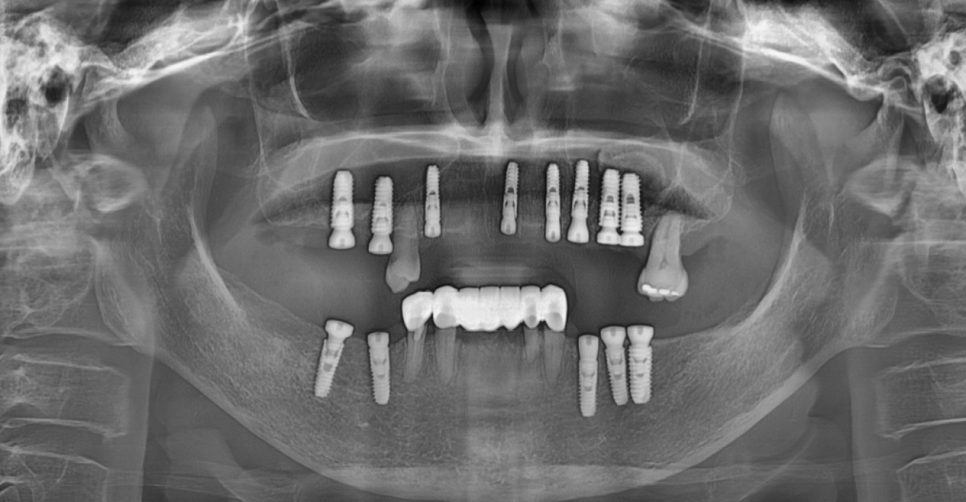

고덕역 치과를 내원하셨던 환자분입니다.

위아래 어금니가 전반적으로 빠진 상황에서

내원하셨는데요.

231018

위아래 전체 임플란트도

임플란트 각도, 깊이가 처음부터 잘 설계가 되어야합니다.

조금이라도 계획과 틀어지면

그 다음 단계가 어려워집니다.